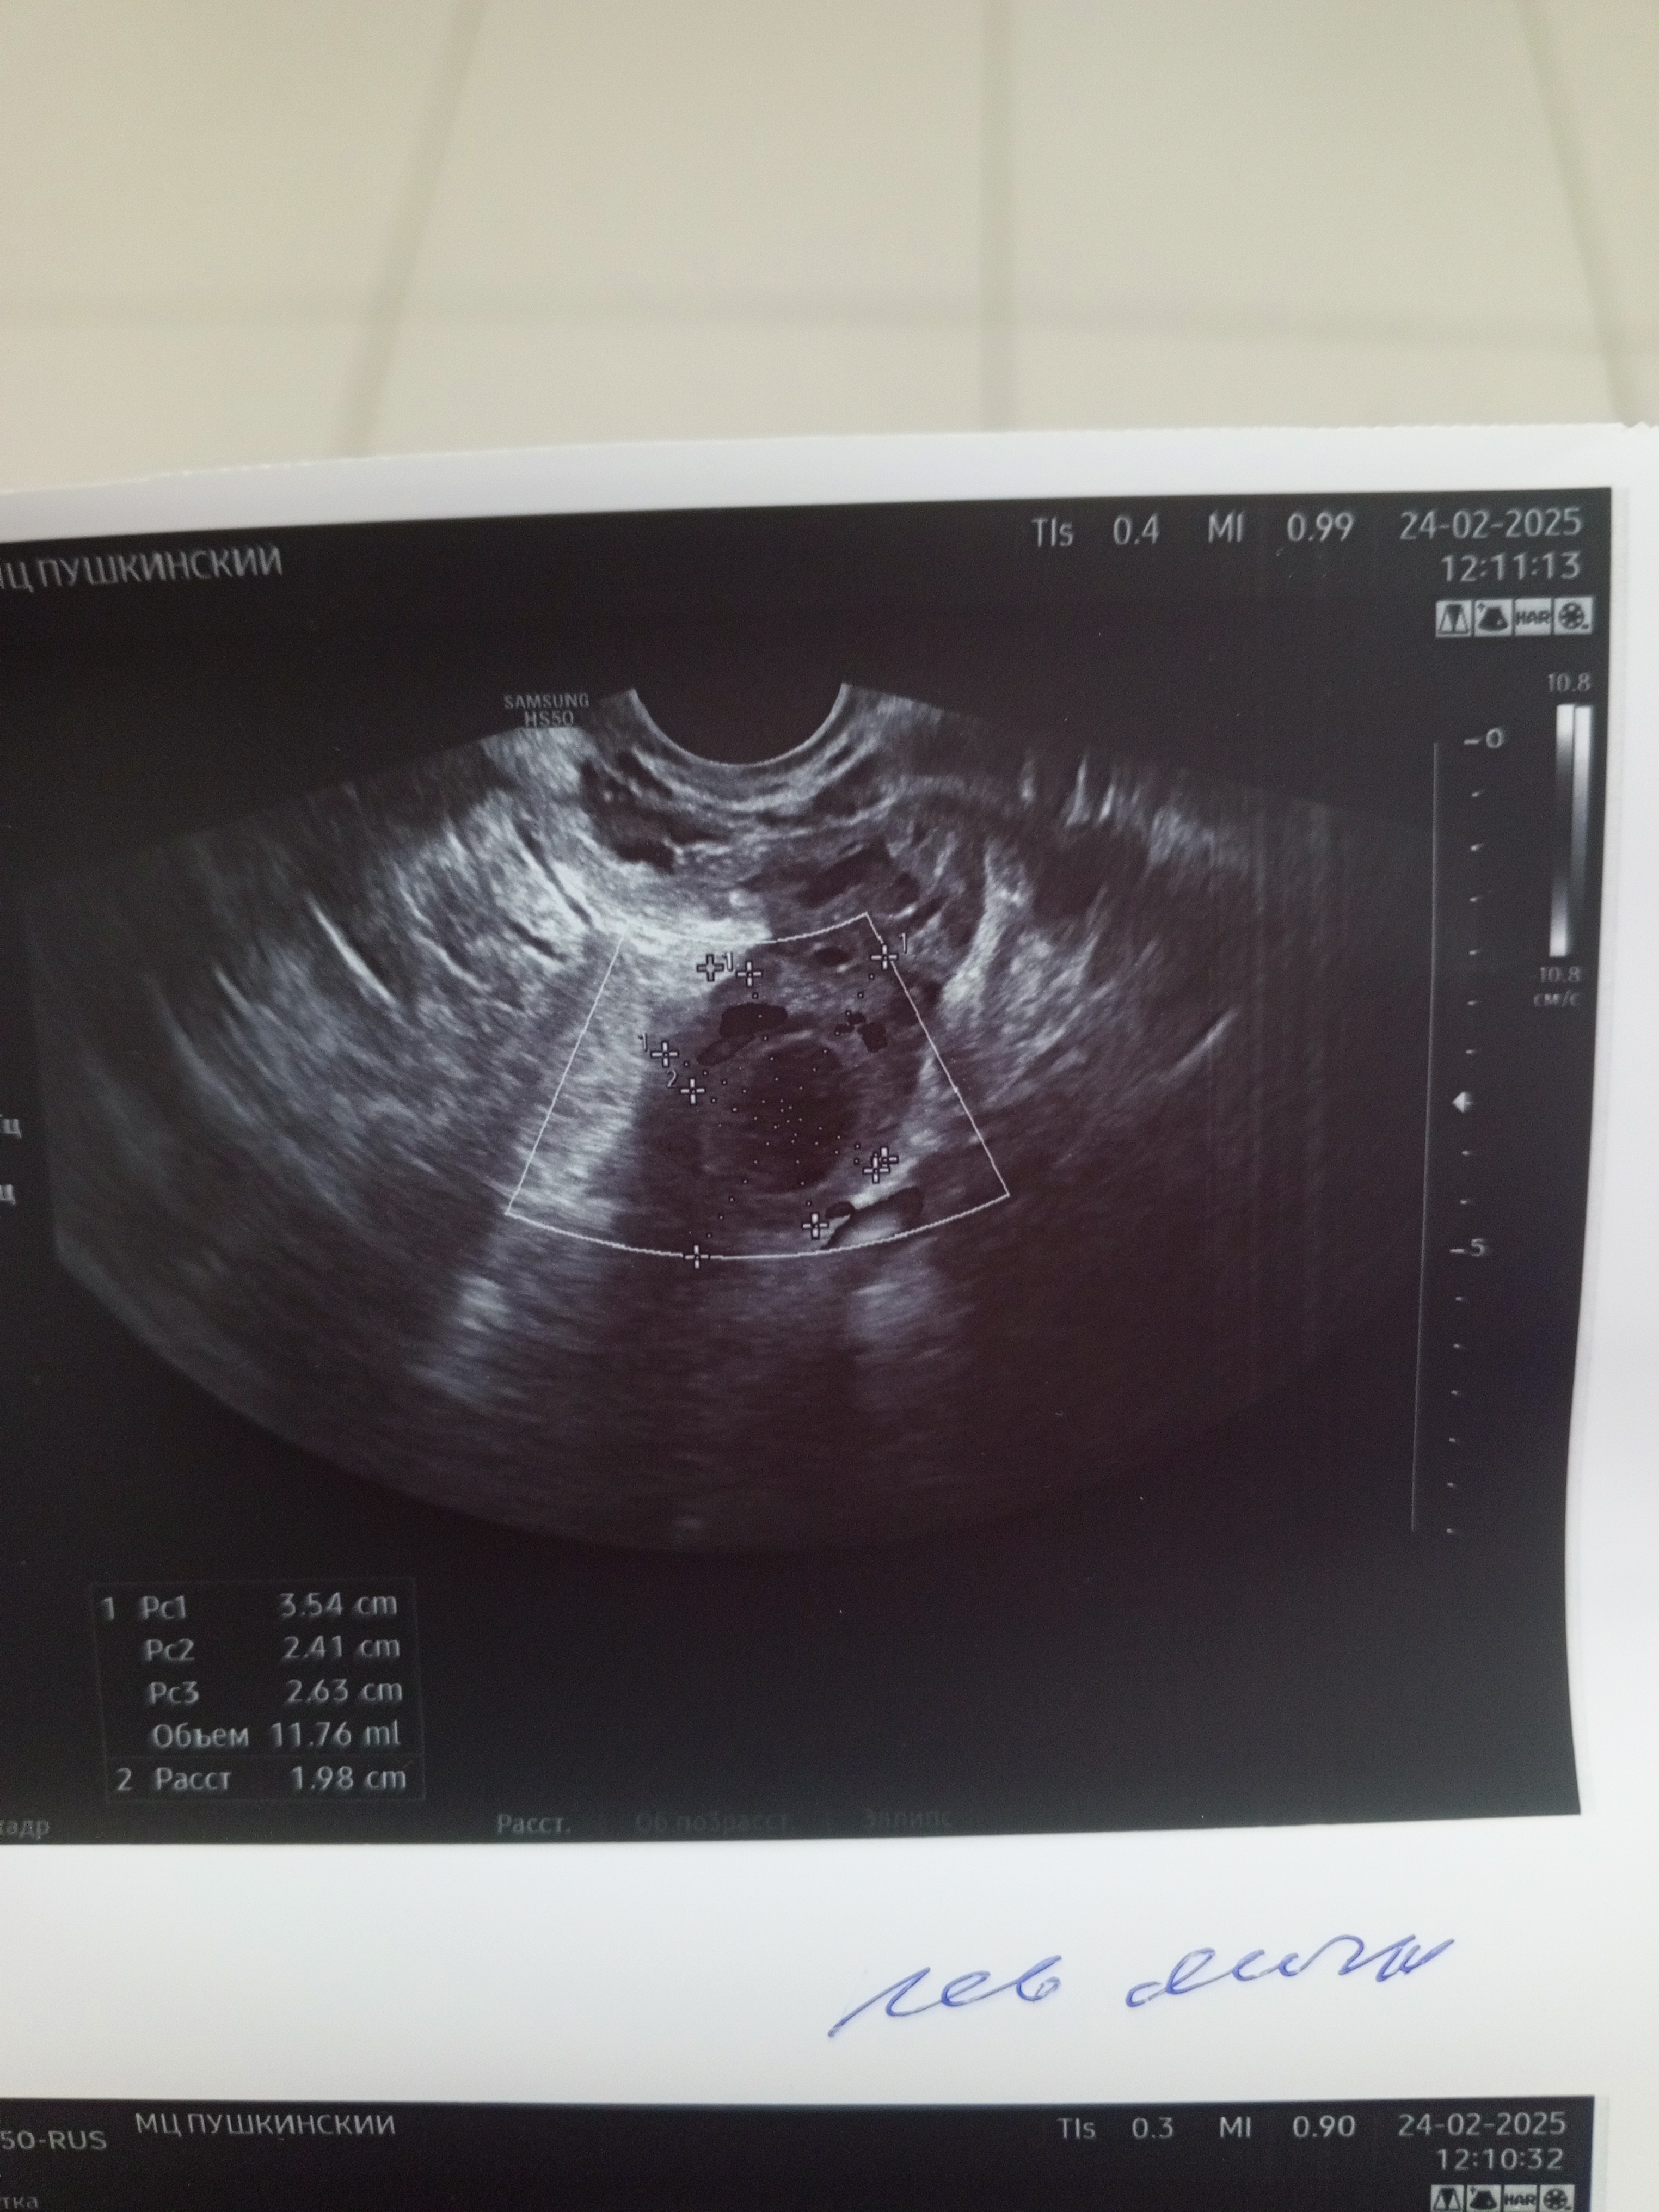

20 дпо это срок 2,6 от зачатия, соответственно 4,6 акушерских УЗИ соответстветствует сроку